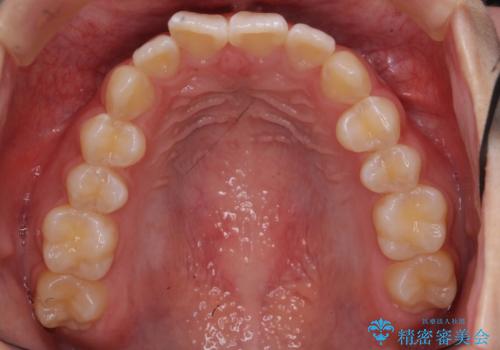

出っ歯 軽度のがたつき インビザラインで

- 20代女性

- インビザライン

- 3年1ヶ月

- 奥歯を後ろに下げる処置をおこなっています。

前歯にオープンバイト気味の症状がありましたが、前歯を後ろに下げることでしっかりかませています。

前歯のずれも治り、しっかり下がりました。